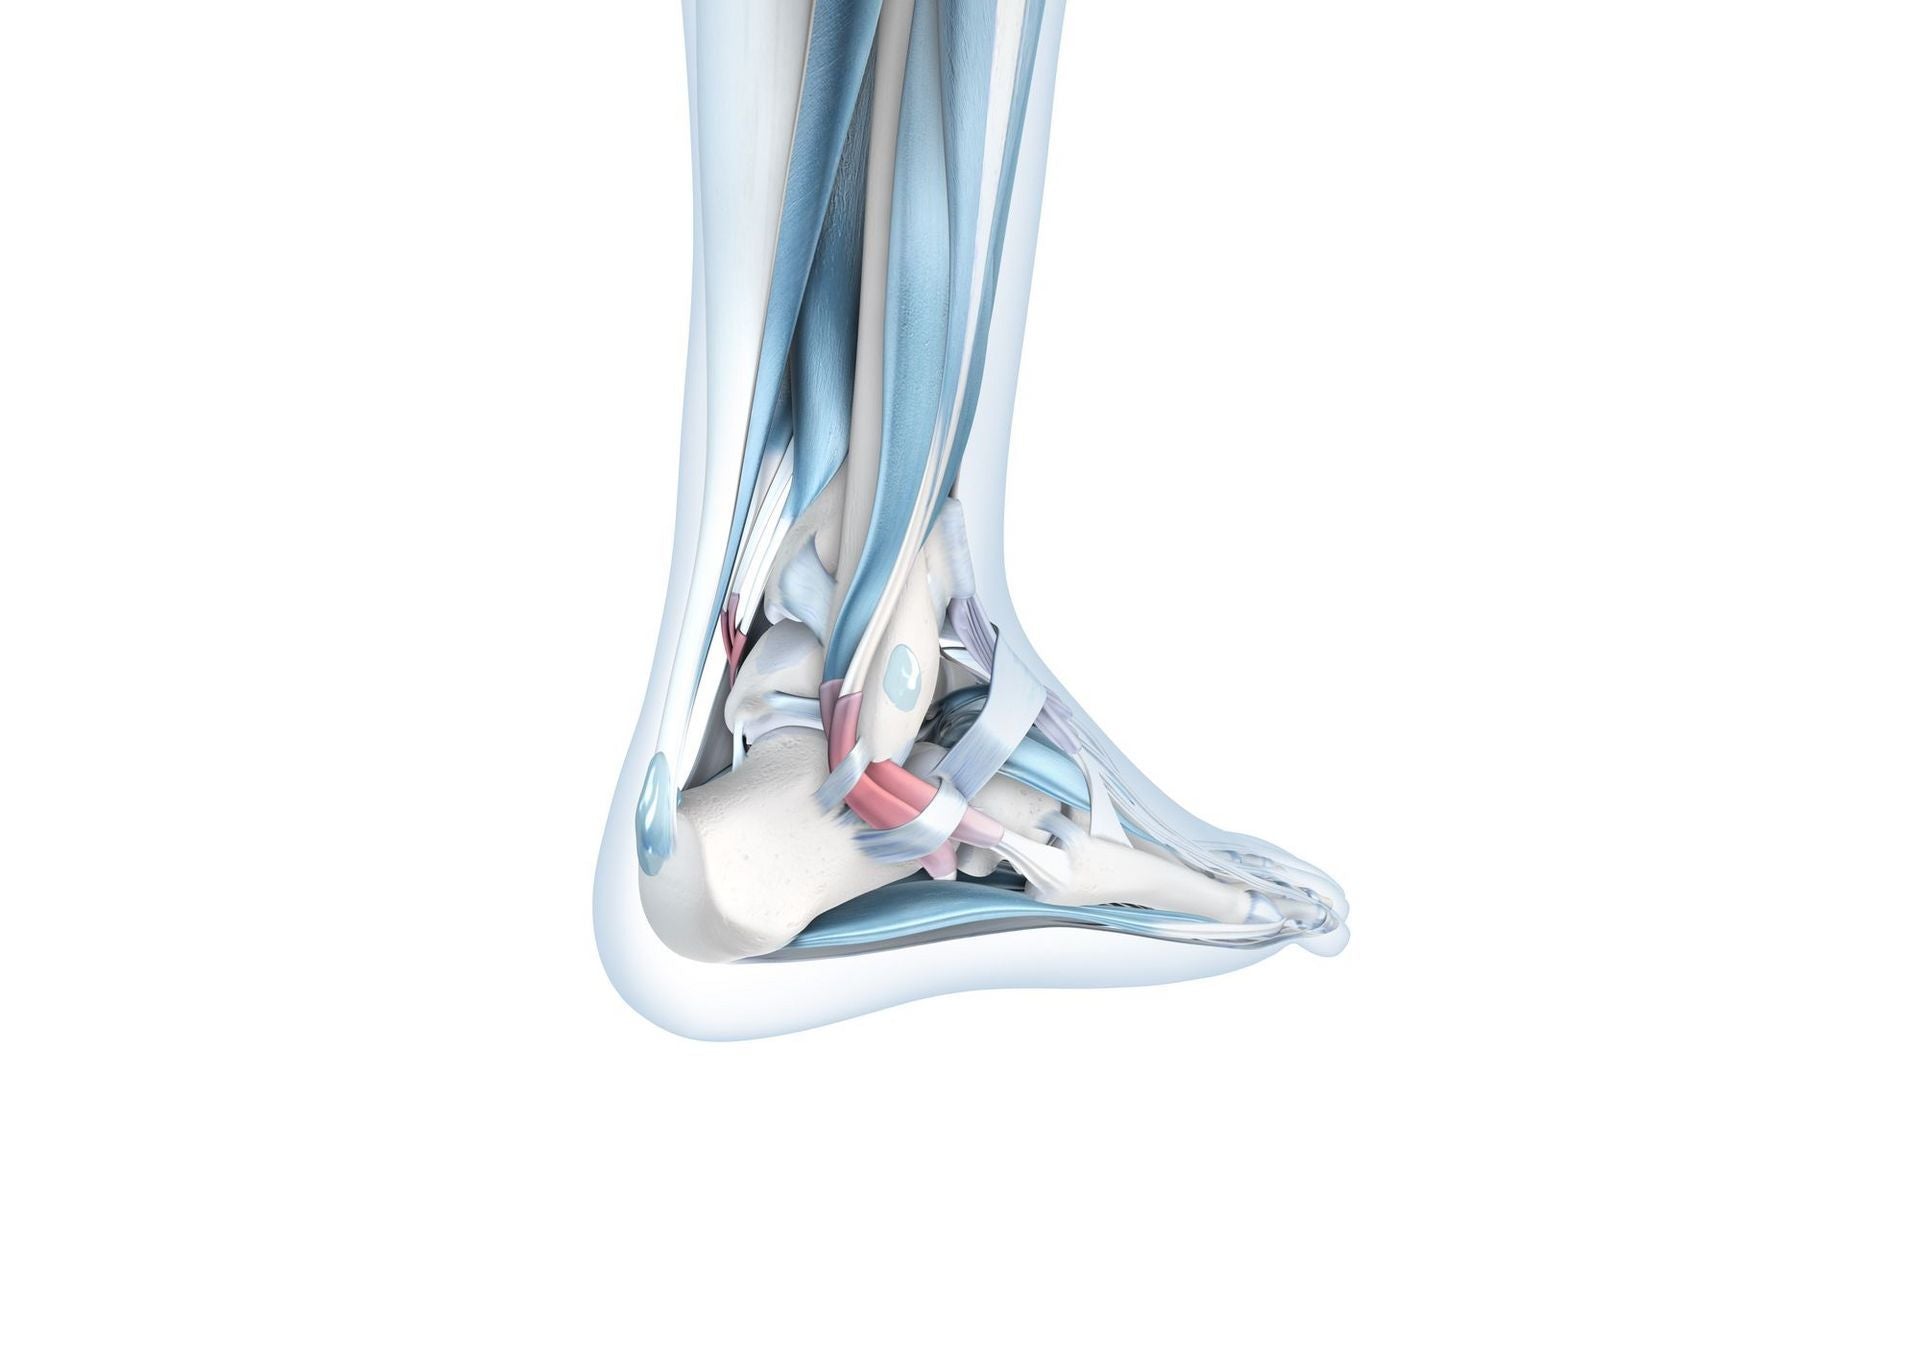

The ankle joint is a complex connection between the leg and tarsal bones. The central ankle bone provides a strong base for both parts of the ankle. A large number of ligaments and connective tissue capsules bind the bones together. The elasticity in the ligaments allows for ease of movement and helps stabilise the ankle joint.

An ankle distortion occurs when one or more joints move beyond their physiological limit of movement. The trauma in most cases damages the joint capsule and is commonly referred to as an injury of the entire capsule-ligament apparatus. The elastic ligaments have a limit, beyond which they can tear partially or, under extreme stress, rupture completely. A patient with an ankle distortion will usually experience restricted movement in the ankle joint and accompanying pain under any stress. The condition can significantly impact daily activities involving walking, running and jumping.

It is highly recommended to get a thorough medical examination, including X-rays and imaging procedures, to examine the nature and extent of the damage incurred. Doctors are then able to provide a better diagnosis with a clear image of the ankle joint structure to refer to.

Depending on the location of the rupture, complications such as accompanying bone fragments may arise. X-rays can detect bone fragments and differentiate between overstretched, partially torn or ruptured ligaments. Injuries to the joint capsule can also be detected more accurately.